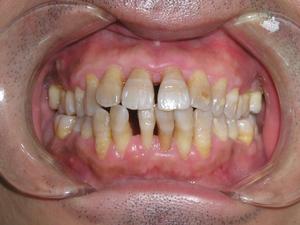

到了 牙周病重期,牙槽骨几乎全部消失 ,牙根会露出大部分,牙齿会异常松动,甚至 脱落。 此时疼痛感强烈,难以咀嚼食物。

重度牙周炎后期,牙根几乎暴露,牙齿变得异常松动